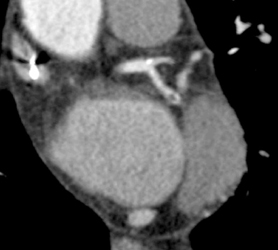

Right and Left Coronary Arteries Arise From A Single Cusp and Orifice